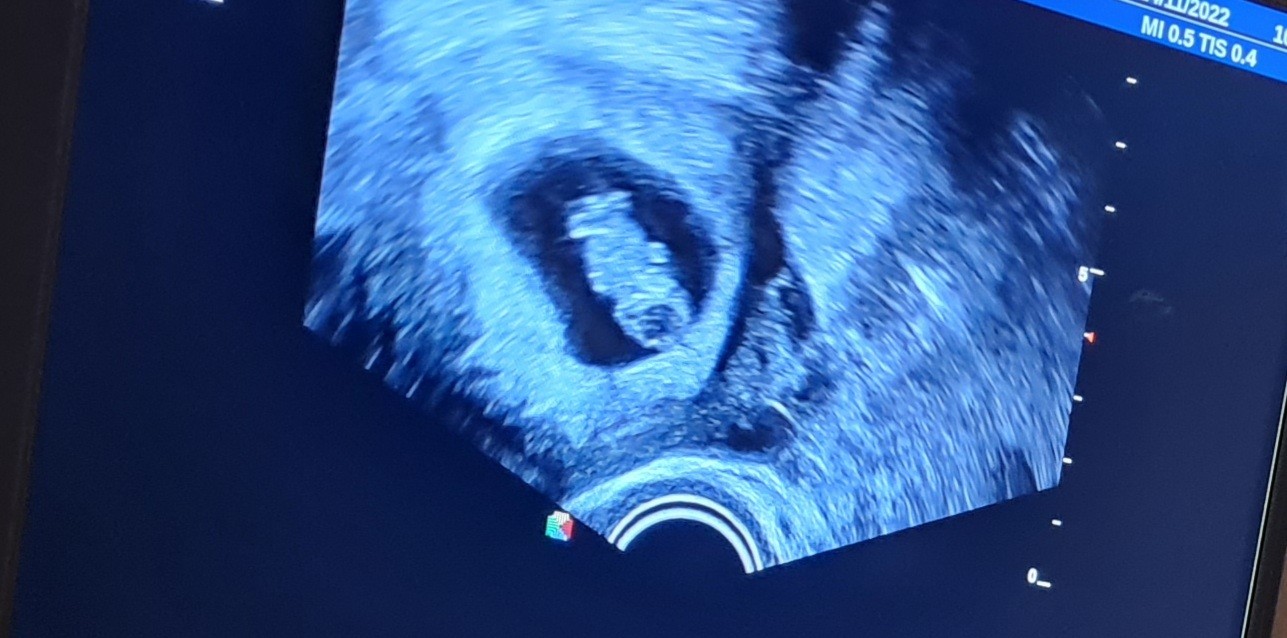

Czy to mogą byc bliźnięta?

Jestem po wizycie, 10 tydzien, na zdjęciu i wideo widzimy z mężem cos jeszcze obok naszego maleństwa. Naczytaliśmy się w nocy ze czesto bliźnięta są nie zauważane, dostrzegane później. Czy to możliwe zeby to były bliźnięta?

Usg było krotkie a on skupił skupił na mierzeniu i szybko skonczyl. Ja tego nie zauważyłam dopiero w domu.mam jeszcze video. I tam też coś się rusza. Jest bardziej zamazane.

Tylko na video tam w środku tez cos się rusza. Usg jest 2 D. Mieszkam w Niemczech, często czytam ze kobiety dowiadują dowiadują w 18 a nawet 29 o bliźniakach. Nie ukrywam że bardzo sie boje ciazy bliźniaczej.

U mnie na pierwszej wizycie nie było widać nic więcej poza jednym pęcherzykiem i echem zarodka ale na kolejnej wizycie w 10 tyg wlansie pojawił się drugi pęcherzyk z zarodkiem i serduszkami. Dziś 32 tydzień ciąży bliźniaczej.